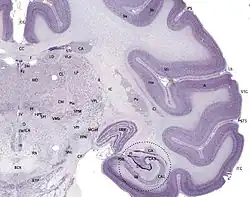

The hippocampus, and dentate gyrus that is folded into the hippocampal archicortex have the shape of a curved, rolled-up tube. The curve of the hippocampus (known as cornu Ammonis) uses the initial letters CA to name the hippocampal subfields CA1-CA4. CA4 is in fact the polymorphic layer or hilus of the dentate gyrus, but CA4 is still sometimes in use to describe the part of CA3 that inserts between the dentate gyrus regions or blades.[17][27]

It can be distinguished as an area where the cortex narrows into a single layer of densely packed pyramidal neurons, which curl into a tight U shape. One edge of the "U" is CA4, the hilus of the dentate gyrus. This is embedded into the backward-facing, flexed dentate gyrus. In humans the hippocampus is described as having an anterior and posterior part; in other primates they are termed rostral and caudal, and in rodent literature they are the ventral and dorsal part.[28] Both parts are of similar composition but belong to different neural circuits.[29] The dentate gyrus combined with other hippocampal regions form a banana-like structure, with the two hippocampi joined at the stems by the commissure of fornix (also called the hippocampal commissure).[19][30] In primates, the part of the hippocampus at the bottom, near the base of the temporal lobe, is much broader than the part at the top. This means that in cross-section the hippocampus can show a number of different shapes, depending on the angle and location of the cut.[31]

In a cross-section of the hippocampus, including the dentate gyrus, several layers will be shown. The dentate gyrus has three layers of cells – the outer molecular layer, the middle granular layer, and the inner polymorphic layer also known as the hilus.[32] The CA3 subfield has the following cell layers known as strata: lacunosum-moleculare, radiatum, lucidum, pyramidal, and oriens. CA2 and CA1 also have these layers except the lucidum stratum.[33]

Hippocampal subfields, and subregions, head, body, and tail, are functionally and anatomically differentiated, and connect differently to other brain regions.[41][42] Their cells are morphologically different.[43] They also have different levels of vulnerability to disease.[41]